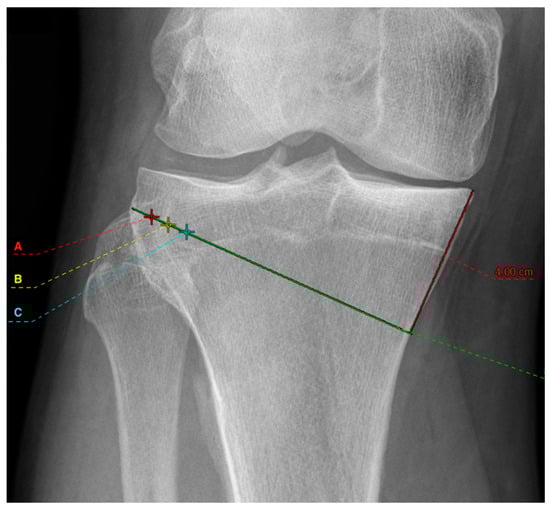

2. Materials and Methods

2.1. Radiographic Assessment